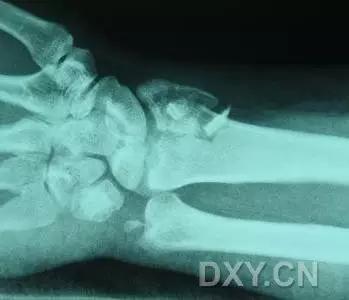

9. Essex-Lopresti 骨折

是桡骨头骨折伴有下尺桡关节脱位,导致骨间膜损伤,桡骨短缩。此种损伤,桡骨头骨折的诊断往往是明确的,容易忽视的是下尺桡关节脱位,特别是早期,下尺桡关节的症状不明显,X 线表示也不明显。

Essex-Lopresti 损伤。前后位(A)和侧位(B)示桡骨头关节内骨折(白色实线箭头);(C~E)伤后 1 个月复诊,患者诉腕关节疼痛,X 线(C,D)发现下尺桡关节脱位,(E)CT 进一步证实损伤的存在 (来源:Radiol Clin North Am. 2015 Jul;53(4):717-36)